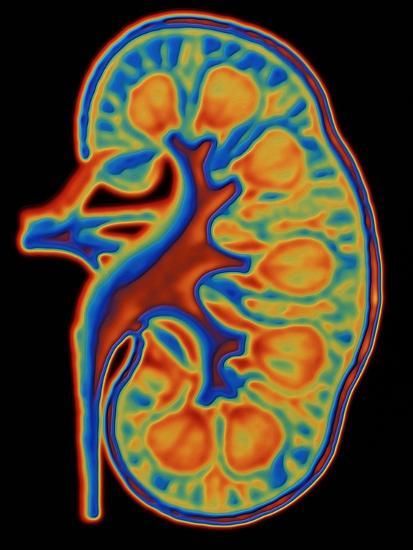

Coloured CT Scan Through a Healthy Human Kidney